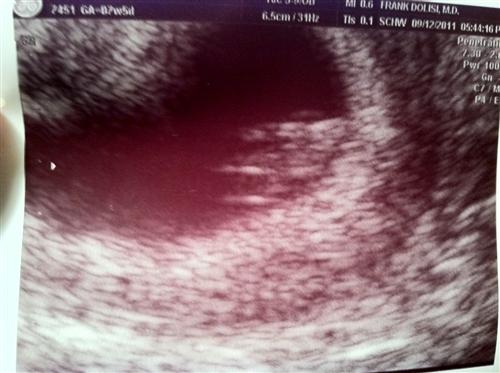

Sono - 7w5d